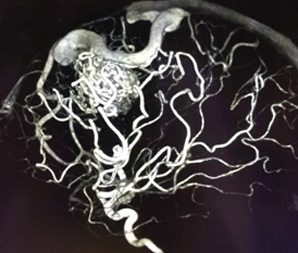

脳動静脈奇形とは、脳にできた異常な血管のかたまり(ナイダス)のことをいいます。通常、脳を栄養する血液は、動脈→毛細血管→静脈の順に流れ、毛細血管から脳へ栄養や酸素を送っています。これに対して、脳動静脈奇形は脳内の動脈と静脈が血管のかたまりであるナイダスで直接つながっており、この中を大量の血液が勢いよく流れています。

- 1)開頭手術によりナイダスを摘出する外科的摘出術

- 2)カテーテルによりナイダスの中を固めてしまう血管内治療(塞栓術)

- 3)放射線によりナイダスを閉塞する定位放射線治療